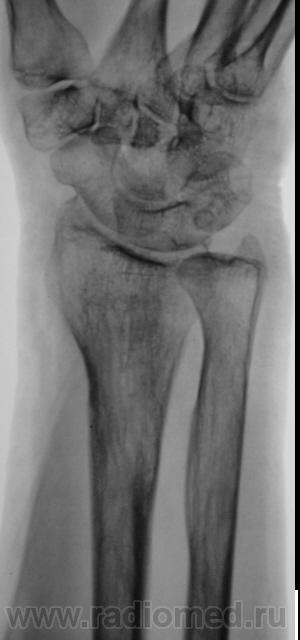

Травма.   Пациент направлен на рентгенографию лучезапястного сустава.